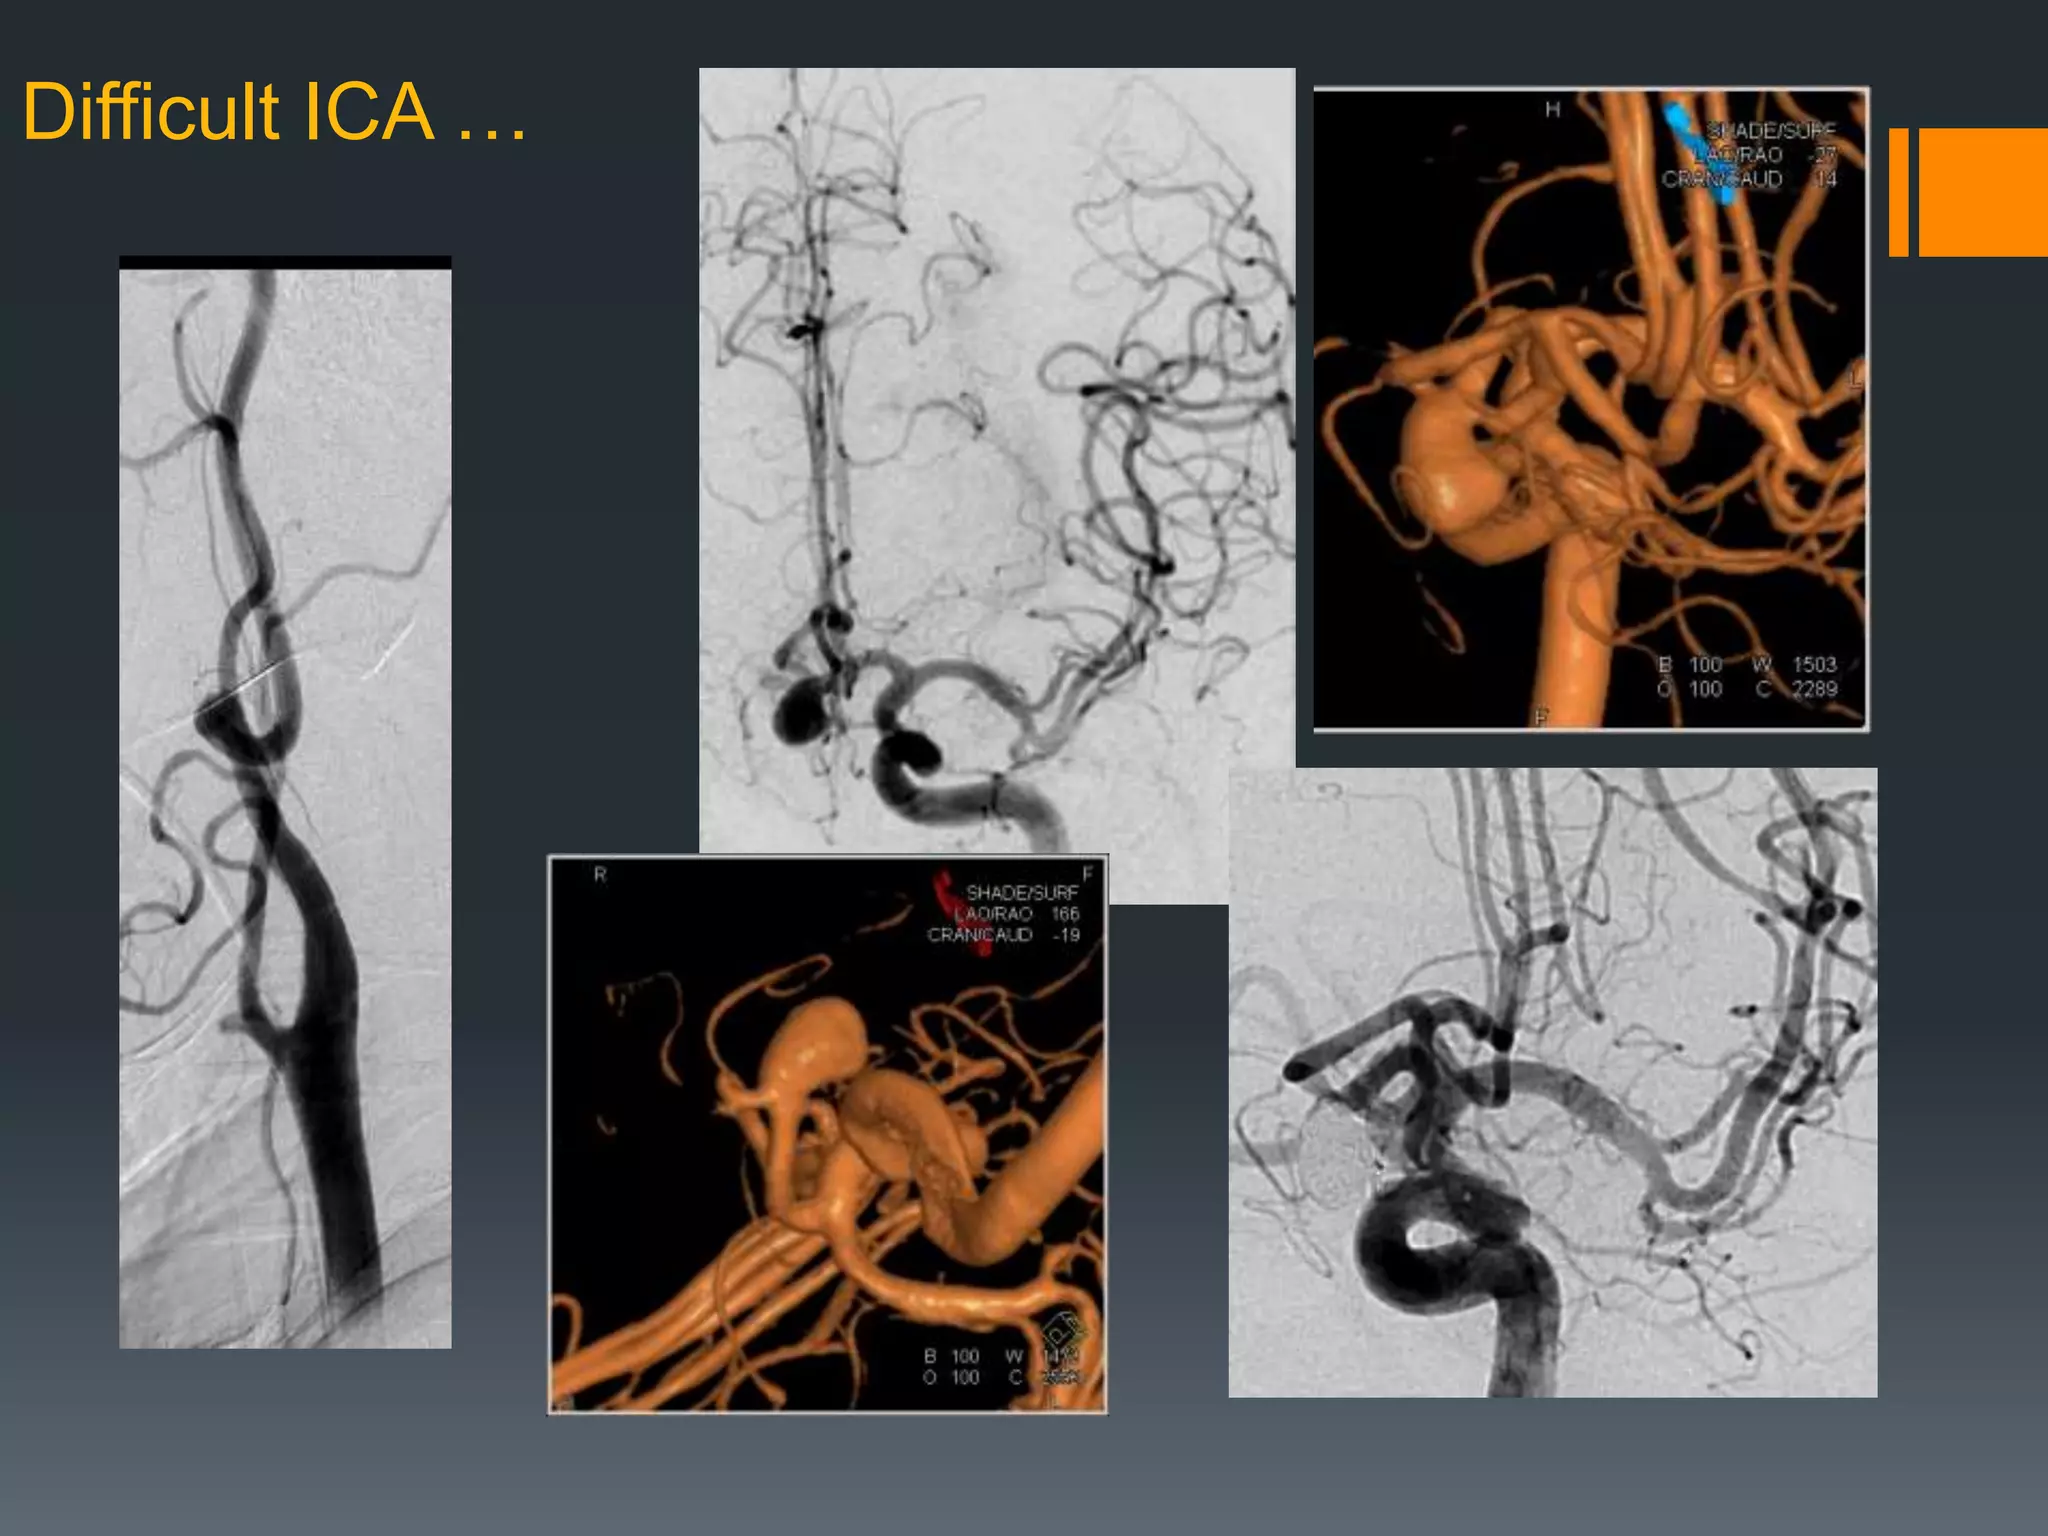

This document discusses tricks and techniques for difficult cannulations during neurointerventional procedures. It outlines strategies for accessing the aortic arch, internal carotid artery (ICA), and areas distal to aneurysms. Long sheaths, distal access catheters, and co-axial techniques are presented as options that have improved cannulation success. Guidance on sheath and catheter selection is provided for different vessel paths. The importance of catheter placement as high as possible in the ICA is emphasized. Reverse curve cannulations are also mentioned. Overall, the document stresses that careful cannulation is critical for procedural success and different strategies may be needed depending on the vessel target.